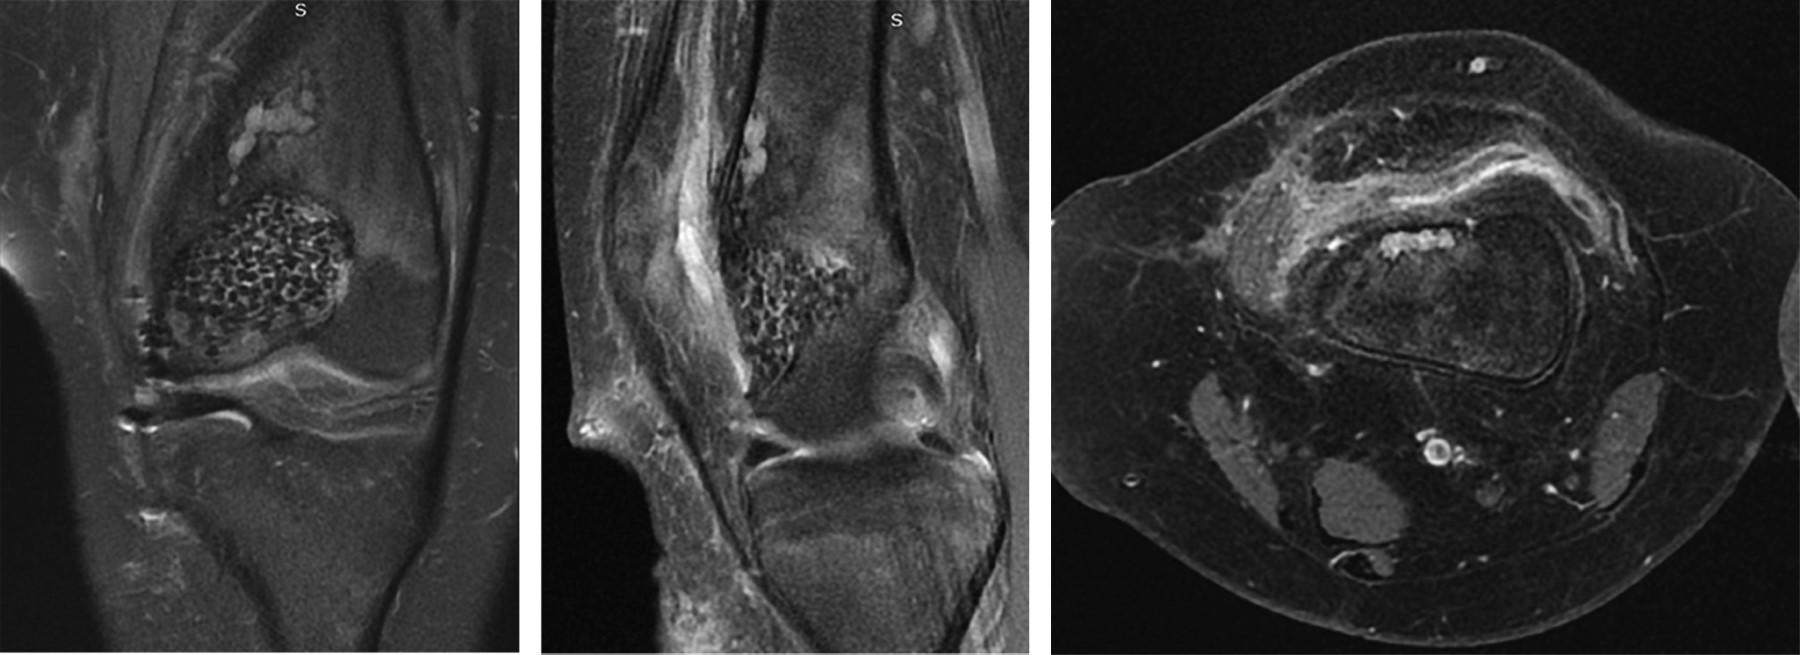

Durante el seguimiento radiológico y clínico estricto, se realizó un control inicial al mes postoperatorio, seguido de controles cada tres meses (Figura 4). Durante el último mes previo al control de los siete meses postoperatorios, la paciente presentó dolor constante afebril y sensación de calor local, sin otros signos de infección. Debido a estos síntomas, se solicitó una RMN de control con contraste, ésta reveló una pequeña lesión endomedular en la metáfisis distal de fémur, sugestiva de un foco de recidiva (Figura 5). Ante este hallazgo, se decidió una nueva intervención en la cual se realizó un segundo curetaje con biopsia, confirmando el diagnóstico de recidiva de condroblastoma. En esta intervención, no se aplicó injerto adicional y se optó por una resección intralesional completa sin adyuvancia.

Figura 4

Figura 5